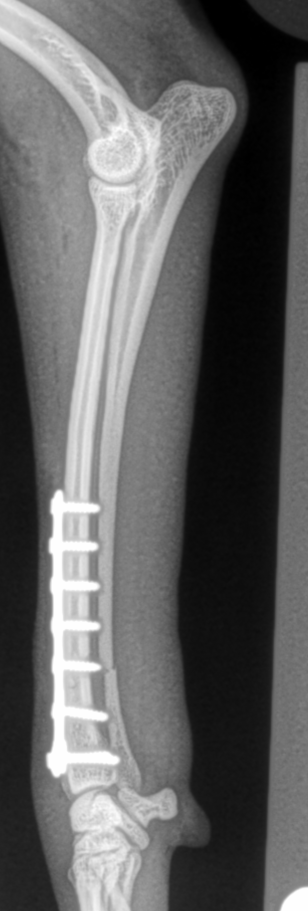

This large segmental tibia-fibula fracture in an Irish Wolfhound was managed by interfragmentary screws and a large medial bone plate applied in a neutralization fashion.